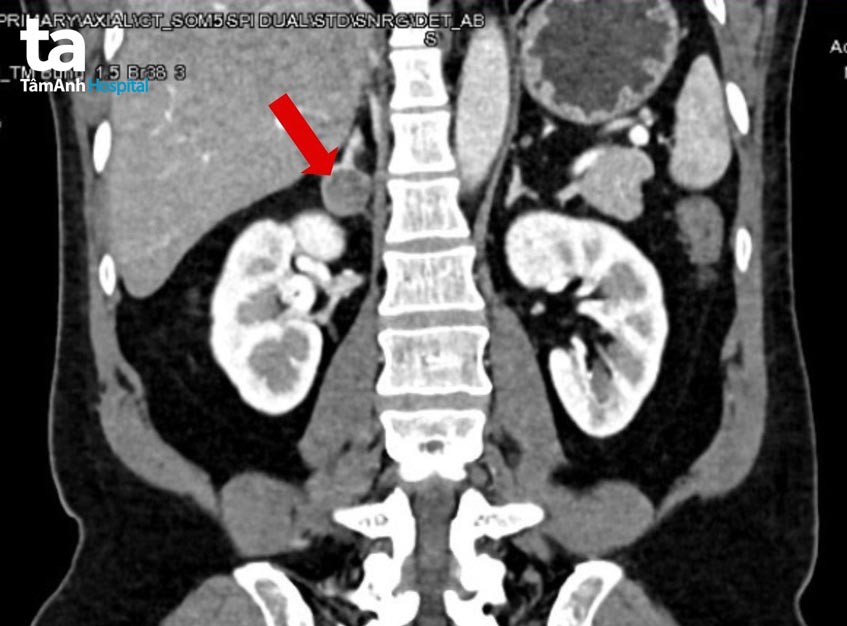

Kết quả cho thấy có một khối u 25 mm ở tuyến thượng thận phải. Bác sĩ Duy nhận định đây chính là nguyên nhân khiến người bệnh có biểu hiện tăng huyết áp bất kiểm soát và chứng hạ kali suốt thời gian qua.

Sau hội chẩn, các bác sĩ quyết định phẫu thuật cắt tuyến thượng thận phải cùng khối u bằng phương pháp nội soi 3D. “Khối u có kích thước tuy nhỏ nhưng lại gây ra hệ lụy lớn đến sức khỏe cho người bệnh”, bác sĩ Nguyễn Hoàng Đức, người trực tiếp phẫu thuật cho người bệnh, nhận định.